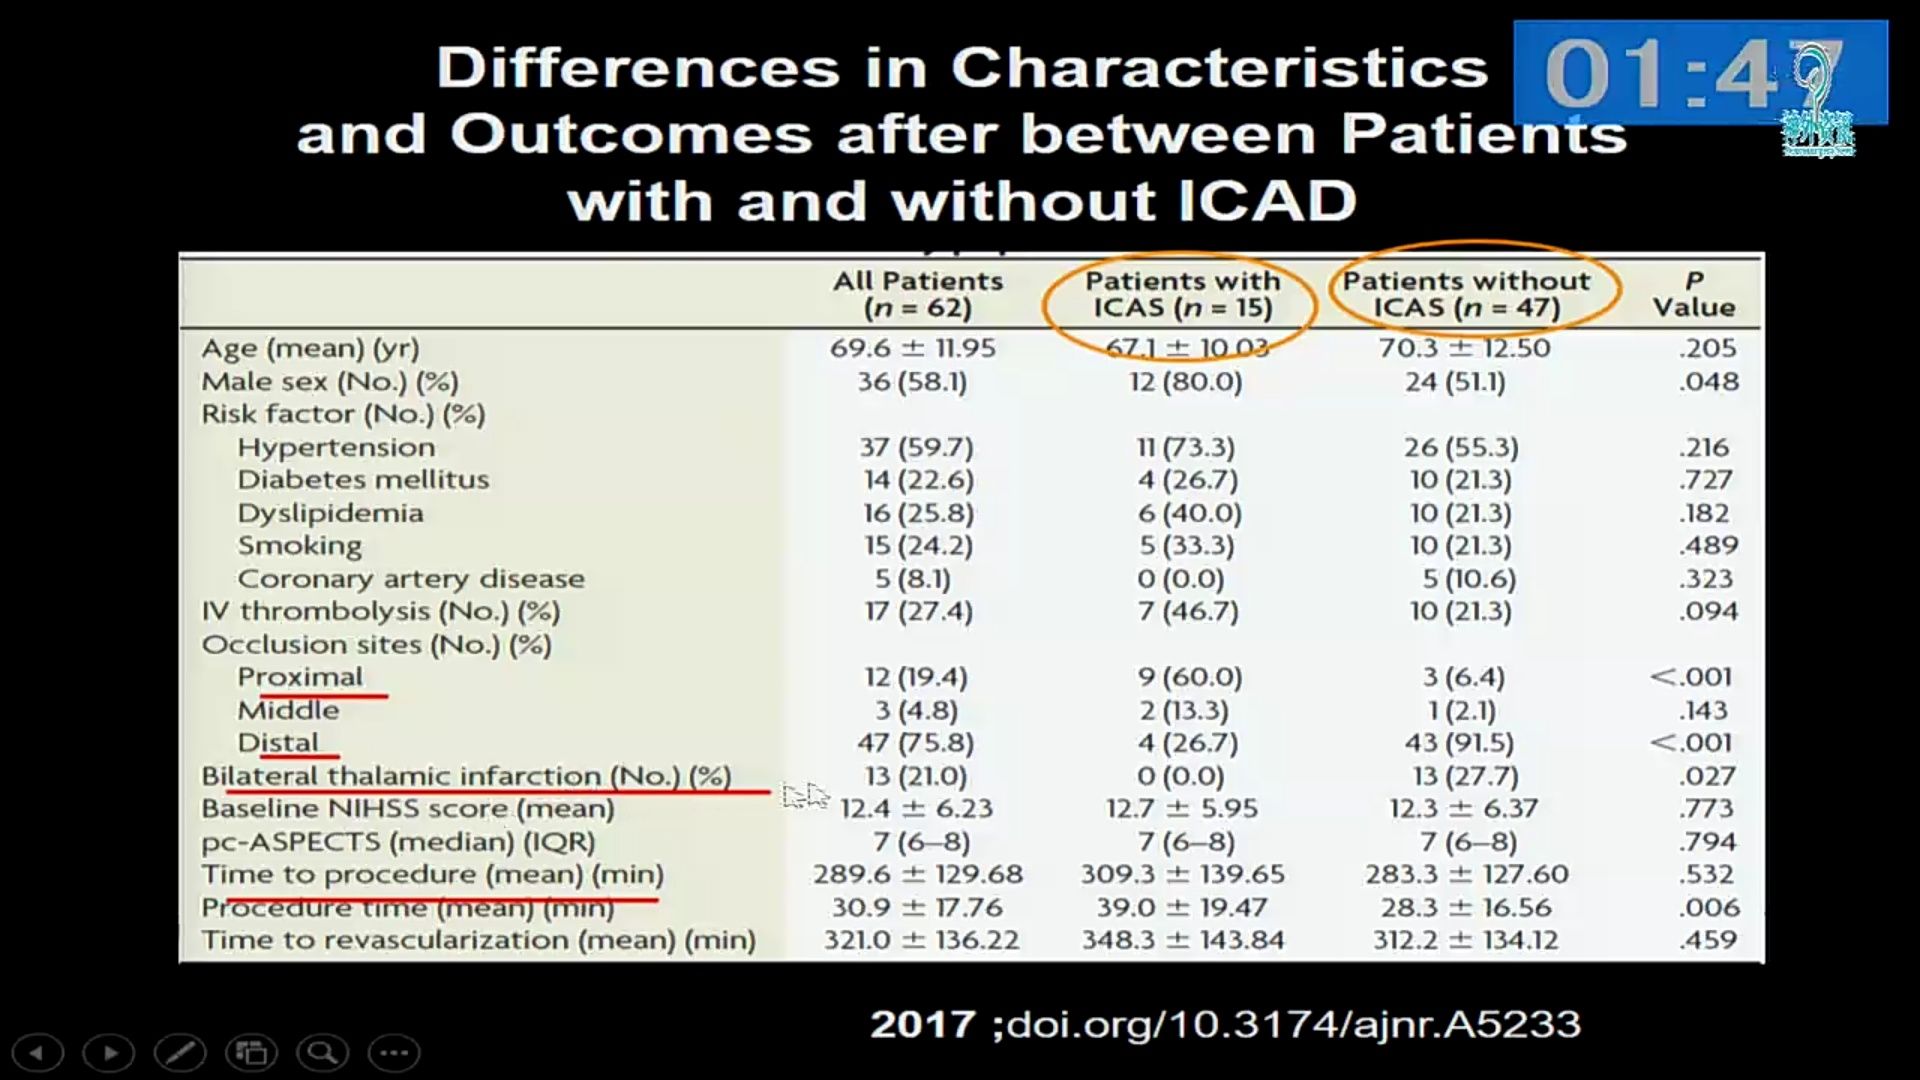

急性椎基底动脉闭塞血管内治疗